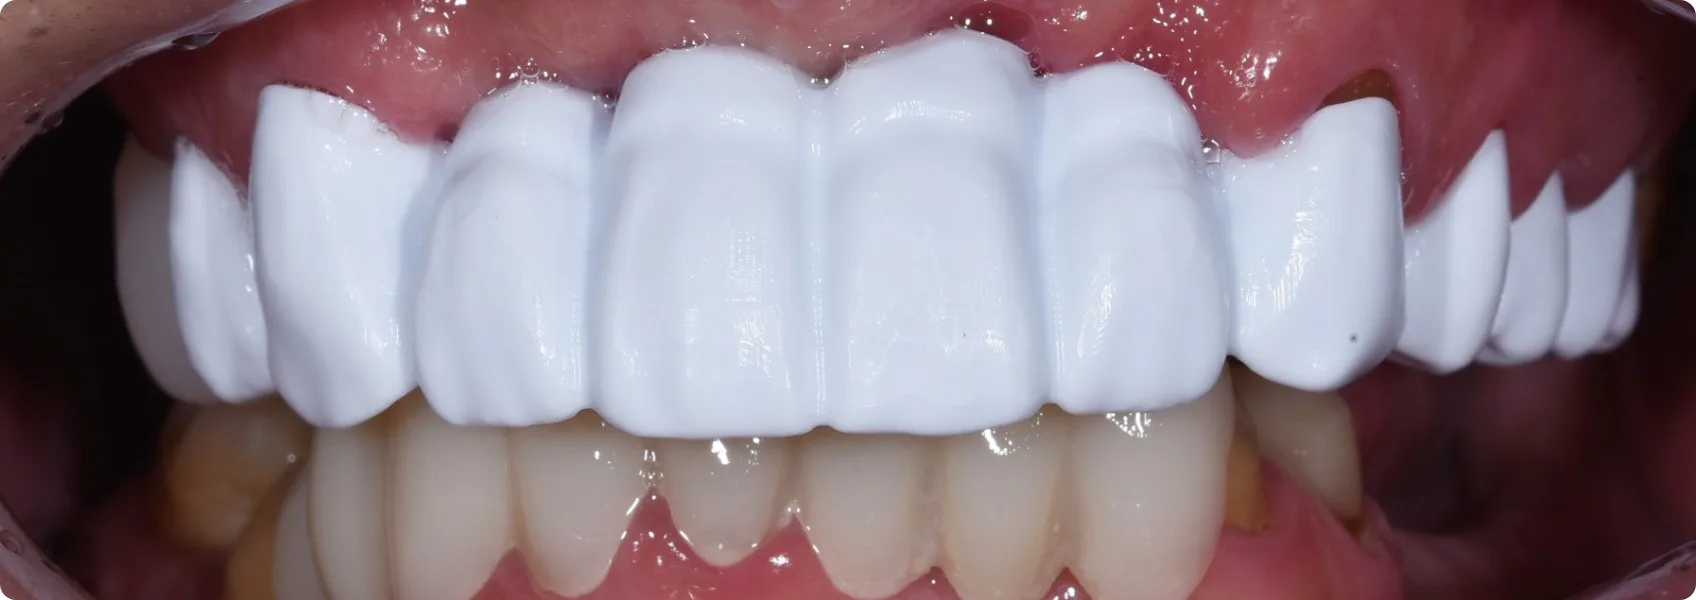

Patrząc na nowy uśmiech Pacjenta, trudno uwierzyć, jak daleką drogę przeszedł. Trudno też uwierzyć, że to nie jego własne, naturalne zęby.

Po wielu miesiącach precyzyjnej pracy, nadszedł ten wyczekiwany moment — oddaliśmy finalny górny most. Mimo że na dolnych zębach Pacjent nosi jeszcze prowizorium, efekt jest absolutnie zachwycający!

Ta odbudowa to dla nas prawdziwe dzieło sztuki. Idealnie odtworzona struktura zębów, sposób, w jaki naturalnie odbijają światło, naturalnie wyglądające dziąsło — każdy najdrobniejszy niuans jest dopracowany tak, by wiernie oddać piękno naturalnego, zdrowego szkliwa.

Dla tego Pacjenta to prawdziwa życiowa rewolucja. Nowe, pełne zęby to nie tylko odzyskanie pięknego uśmiechu i pewności siebie, ale przede wszystkim powrót do normalności — swobodnego jedzenia, wyraźnego mówienia i życia bez ciągłego bólu.